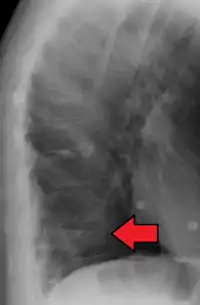

X-ray of the lumbar spine with a compression fracture of the third lumbar vertebra.

Compression fracture of T12